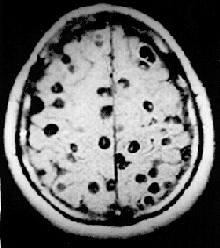

![]() Цистицерки в головном мозге. Магнитно-резонансное изображение. | |

Чаще всего (более 60 %) цистицерк попадает в головной мозг, реже в скелетные мышцы и глаза. Продолжительность жизни паразита в мозге от 5 до 30 лет. В большинстве случаев в головном мозге имеются сотни и тысячи паразитов, однако встречаются и единичные цистицерки. Они локализуются в мягких мозговых оболочках на основании мозга, в поверхностных отделах коры, в полости желудочков, где они могут свободно плавать. Погибая, паразит обызвествляется, однако, оставаясь в мозге, поддерживает хронический воспалительный процесс.

Диагностировать цистицеркоз головного мозга исключительно трудно из-за отсутствия патогномоничных симптомов. В постановке диагноза опираются на следующие особенности заболевания: множественность симптомов, указывающая на многоочаговое поражение мозга, преобладание явлений раздражения, наличие признаков повышения внутричерепного давления, смена тяжелого состояния больного периодами благополучия. Диагностике помогают рентгенографические данные, КТ, МРТ, а также эозинофилия крови и цереброспинальной жидкости, положительная РСК с цистицеркозным антигеном.